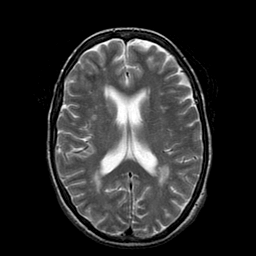

Metastatic Adenocarcinoma of the Colon: T2-weighted MR -- Slice #14

[Home][Help][Clinical] Slice 14